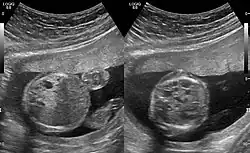

CPAMs are often identified during routine prenatal ultrasonography. Identifying characteristics on the sonogram include: an echogenic (bright) mass appearing in the chest of the fetus, displacement of the heart from its normal position, a flat or everted (pushed downward) diaphragm, or the absence of visible lung tissue.

CPAMs are classified into three different types based largely on their gross appearance. Type I has a large (>2 cm) multiloculated cysts. Type II has smaller uniform cysts. Type III is not grossly cystic, referred to as the "adenomatoid" type. Microscopically, the lesions are not true cysts, but communicate with the surrounding parenchyma. Some lesions have an abnormal connection to a blood vessel from an aorta and are referred to as "hybrid lesions."

Imaging

The earliest point at which a CPAM can be detected is by prenatal ultrasound. The classic description is of an echogenic lung mass that gradually disappears over subsequent ultrasounds. The disappearance is due to the malformation becoming filled with fluid over the course of the gestation, allowing the ultrasound waves to penetrate it more easily and rendering it invisible on sonographic imaging. When a CPAM is rapidly growing, either solid or with a dominant cyst, they have a higher incidence of developing venous outflow obstruction, cardiac failure and ultimately hydrops fetalis. If hydrops is not present, the fetus has a 95% chance of survival. When hydrops is present, risk of fetal demise is much greater without in utero surgery to correct the pathophysiology. The greatest period of growth is during the end of the second trimester, between 20 and 26 weeks.

A measure of mass volume divided by head circumference, termed cystic adenomatoid malformation volume ratio (CVR) has been developed to predict the risk of hydrops. The lung mass volume is determined using the formula (length × width × anteroposterior diameter ÷ 2), divided by head circumference. With a CVR greater than 1.6 being considered high risk. Fetuses with a CVR less than 1.6 and without a dominant cyst have less than a 3% risk of hydrops. After delivery, if the patient is symptomatic, resection is mandated. If the infant is asymptomatic, the need for resection is a subject of debate, though it is usually recommended. Development of recurrent infections, rhabdomyosarcoma, adenocarcinomas in situ within the lung malformation have been reported.[4]